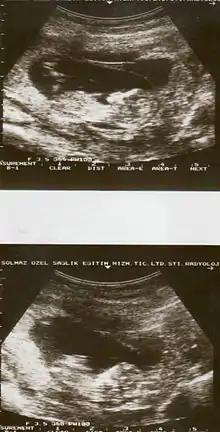

Ultrasound showing placental abruption

Placental abruption is suspected when a pregnant mother has sudden localized abdominal pain with or without bleeding. The fundus may be monitored because a rising fundus can indicate bleeding. An ultrasound may be used to rule out placenta praevia but is not diagnostic for abruption.[8] The diagnosis is one of exclusion, meaning other possible sources of vaginal bleeding or abdominal pain have to be ruled out in order to diagnose placental abruption.[5] Of note, use of magnetic resonance imaging has been found to be highly sensitive in depicting placental abruption, and may be considered if no ultrasound evidence of placental abruption is present, especially if the diagnosis of placental abruption would change management.[16]